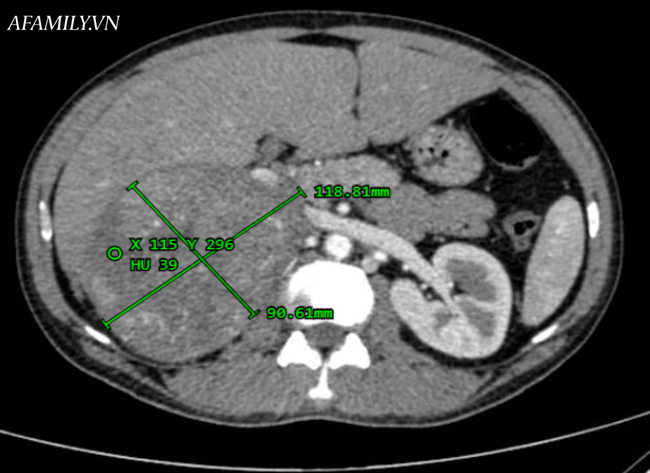

Qua thăm khám lâm sàng, bệnh nhân được ghi nhận bị cao huyết áp nhẹ 130/80 mmHg, nữ hóa tuyến vú, không ghi nhận dấu hiệu hội chứng Cushing. Kết quả chụp CT bụng cho thấy có tổn thương vùng giữa gan và thận phải kích thước lớn, chèn ép và đẩy thận phải xuống thấp.

Quá trình phẫu thuật, bệnh nhân mất 1.200ml máu. Khối u thượng thận phải được đưa ra ngoài có đường kính 20x30cm, có nhiều mạch máu, tăng sinh dính dọc tĩnh mạch chủ dưới.